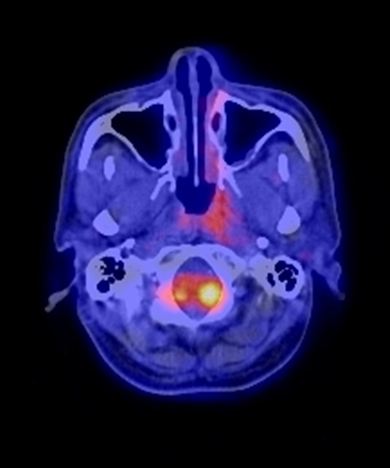

Trước điều trị: khối u vòm lớn tăng hấp thu FDG mạnh.

Sau điều trị: u tan hết, không thấy tổ chức tăng hấp thu FDG vùng vòm.

Hình 8: Bệnh nhân Trịnh Thị Thúy L., nữ, 44 tuổi, vào viện vì đau đầu, chảy máu mũi, được chẩn đoán là K vòm T2N1M0, UTBM không biệt hóa. Được điều trị: PET/CT mô phỏng lập kế hoạch xạ trị IMRT (7 trường chiếu, 43 segments). Sau điều trị hết đau đầu và chảy máu mũi.

Trước điều trị: khối u thành vòm trái tăng hấp thu FDG mạnh: max SUV=14,3.

Sau điều trị: u tan hết, còn viêm nhẹ thành vòm sau xạ trị, max SUV=2,1.

Hình 9: Bệnh nhân Trương M. D., 52 tuổi, vào viện vì ngạt mũi trái, chảy máu mũi, được chẩn đoán là K vòm T2N1M0, UTBM không biệt hóa. Được điều trị: PET/CT mô phỏng lập kế hoạch xạ trị IMRT (7 trường chiếu, 49 segments). Sau điều trị bệnh khỏi hoàn toàn.

Hình 10: Bệnh nhân Đỗ V.Th., nam, 51 tuổi. Vào viện vì xì máu mũi, được chẩn đoán là K vòm T2N0M0, UTBM không biệt hóa. Được điều trị: PET/CT mô phỏng lập kế hoạch xạ trị IMRT (7 trường chiếu, 35 segments). Sau điều trị bệnh khỏi hoàn toàn. (2 hình ở trên: hình PET/CT và MIP của bệnh nhân sau điều trị không phát hiện tổn thương nào; 2 hình ở dưới: hình PET/CT và MIP của bệnh nhân trước điều trị thấy khối u thành vòm phải tăng hấp thu FDG mạnh).